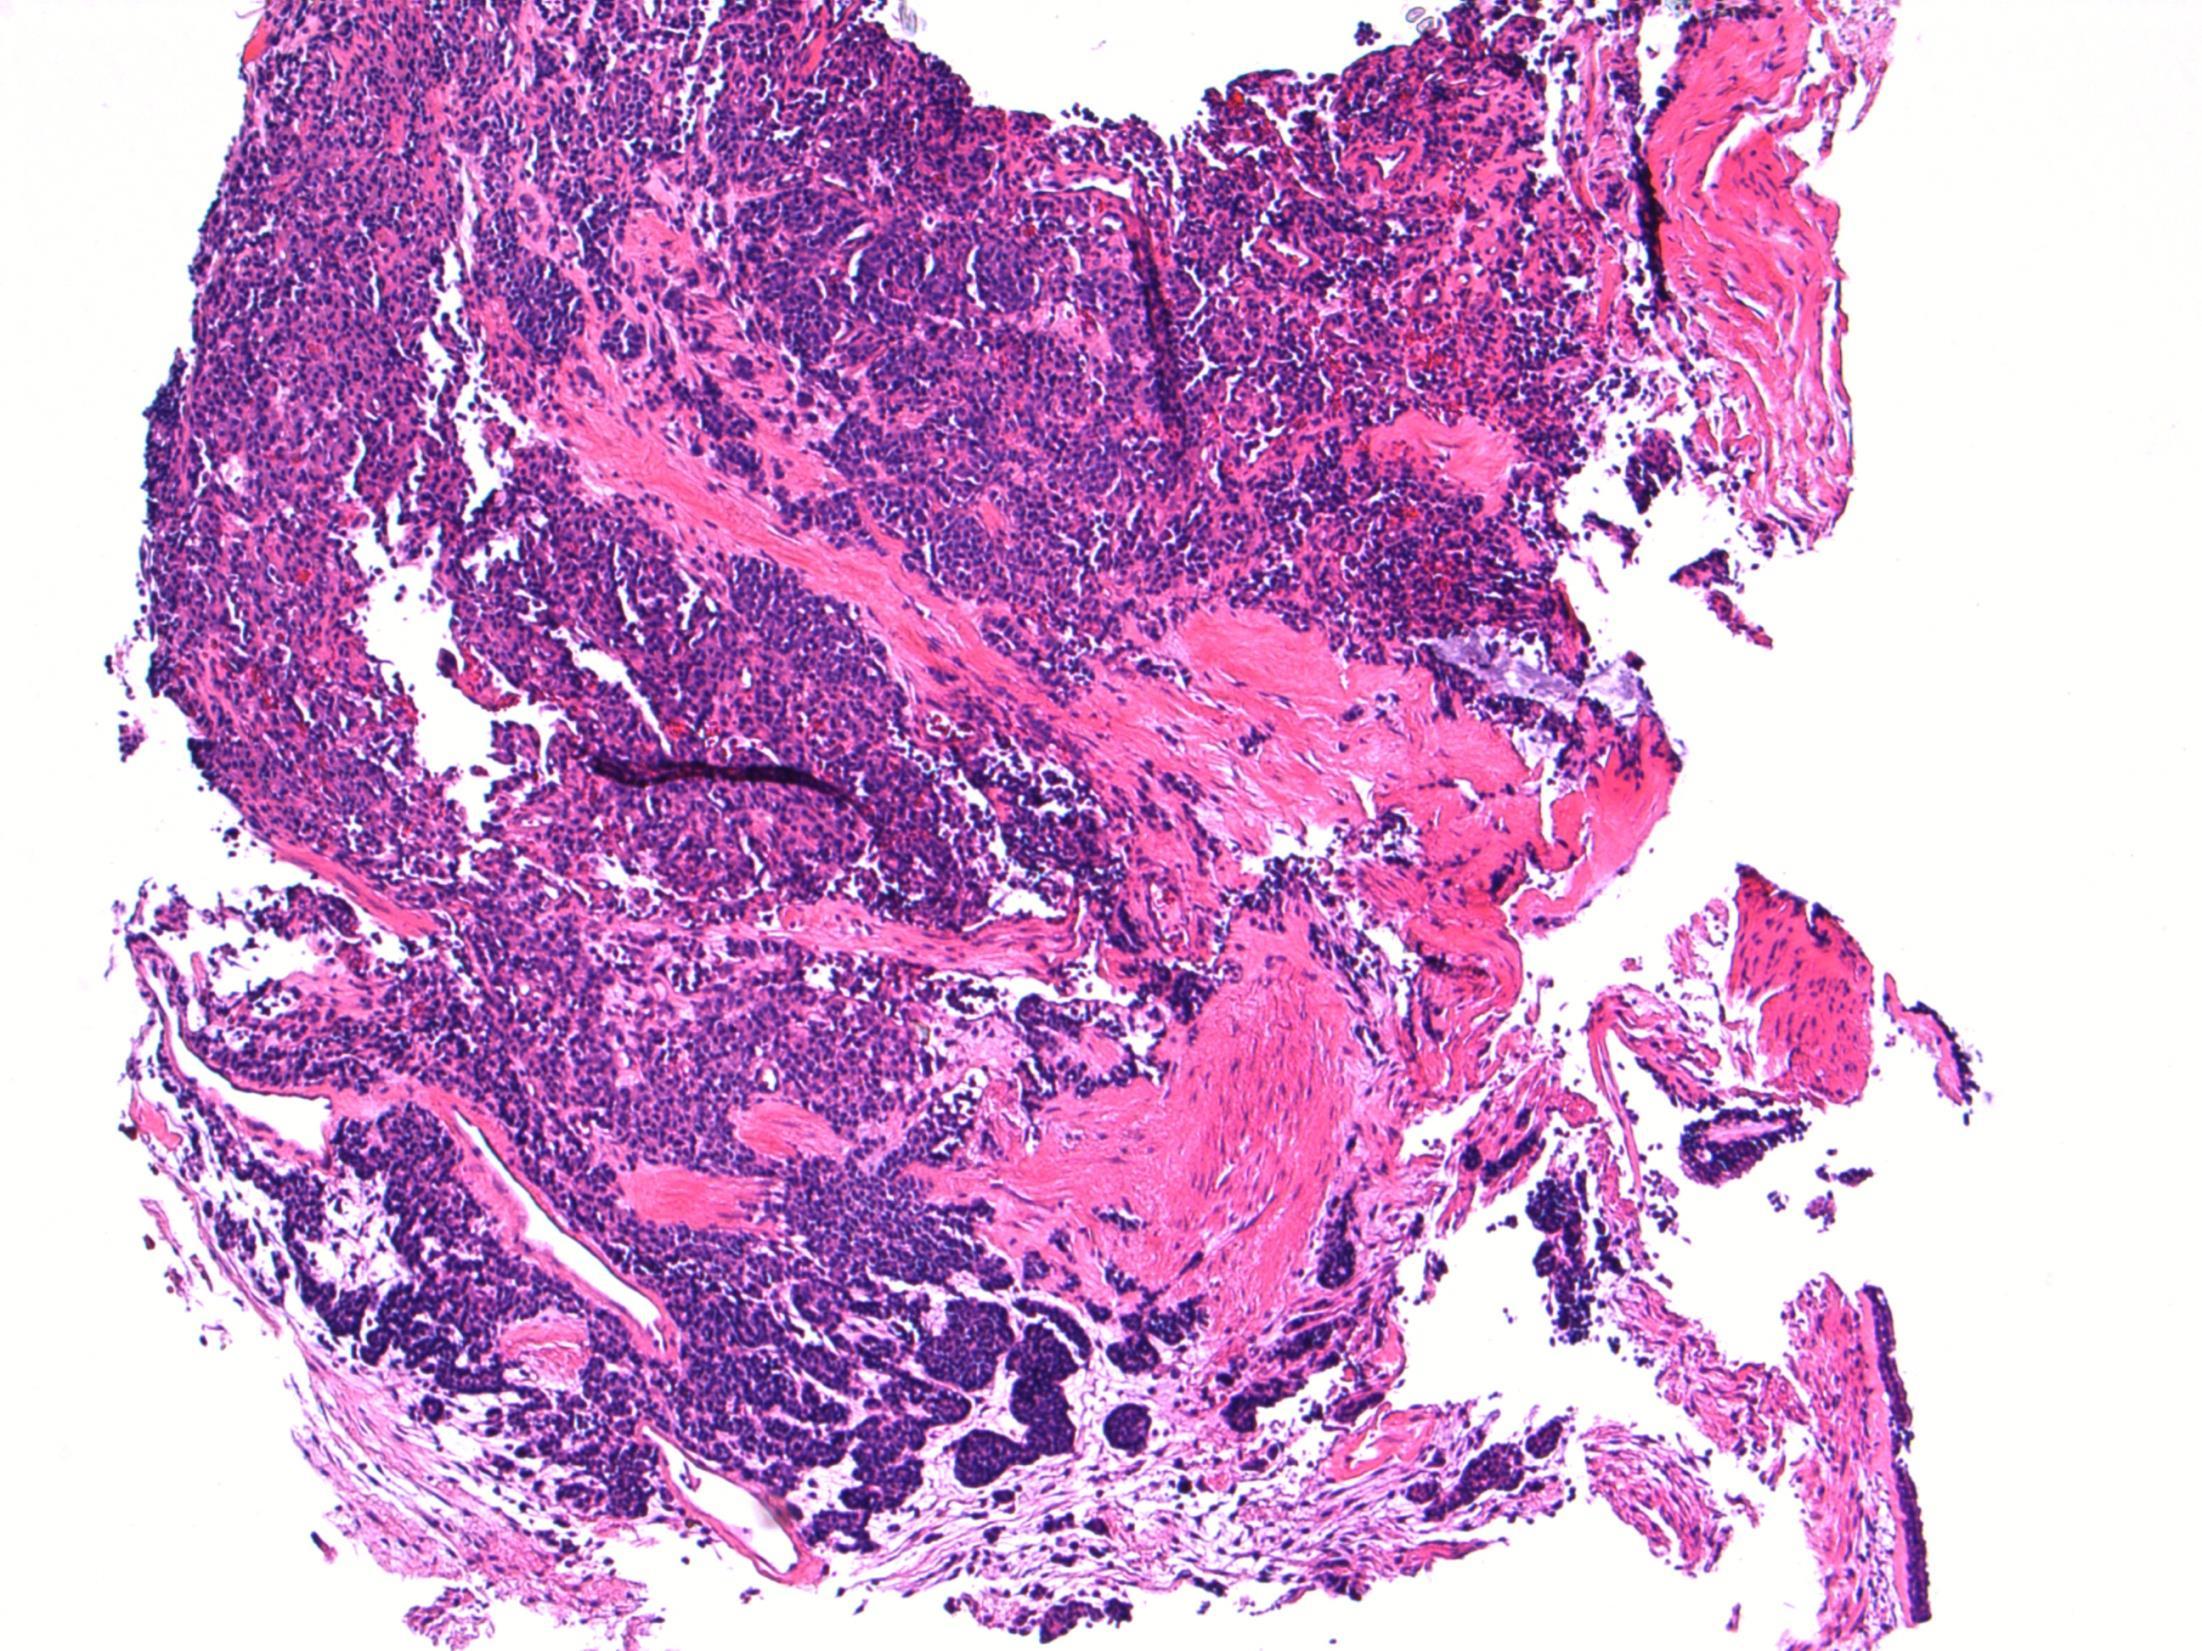

28F Acute abdominal pain. Laparoscopy showed torted large right ovary, ?Ovarian cyst. Excised. Macro- Ovary measuring 9x8x5cm with a solid and soft cut surface. No cyst seen.

Case

7 •

• Ovary – Massive ovarian oedema

7

Massive ovarian oedema

Description: Diffuse oedema of medulla and inner cortex; relative sparing of outer cortex. Associated RBC extravasation, congestion, inflammation. No cyst seen. No evidence of malignancy.

Diagnosis: Massive ovarian oedema

Differential Diagnosis:

• Fibroma/ fibrothecoma. May show marked oedema but tumour usually replaces entire ovary with no sparing at edges.

• Krukenberg tumour. Can look similar macroscopically and malignant cells can be sparse. Usually older females but can occur in younger females.

Plan:

• Extra blocks to exclude sparse tumour cells.

• Correlate with radiology.

Comments:

Partial torsion of an otherwise normal ovary.

Common in 2nd and 3rd decade – like this case.

Macroscopically a featureless myxoid enlarged ovary (correlates with macro features).

3.5 Cause, prognosis, treatment etc 3.0 Differential diagnostic considerations 2.5 Description with diagnosis 2.0 Other benign diagnosis with no consideration of ovarian oedema 1.5 Differential diagnosis, favouring malignant 1.0 Definite malignant diagnosis Case 7